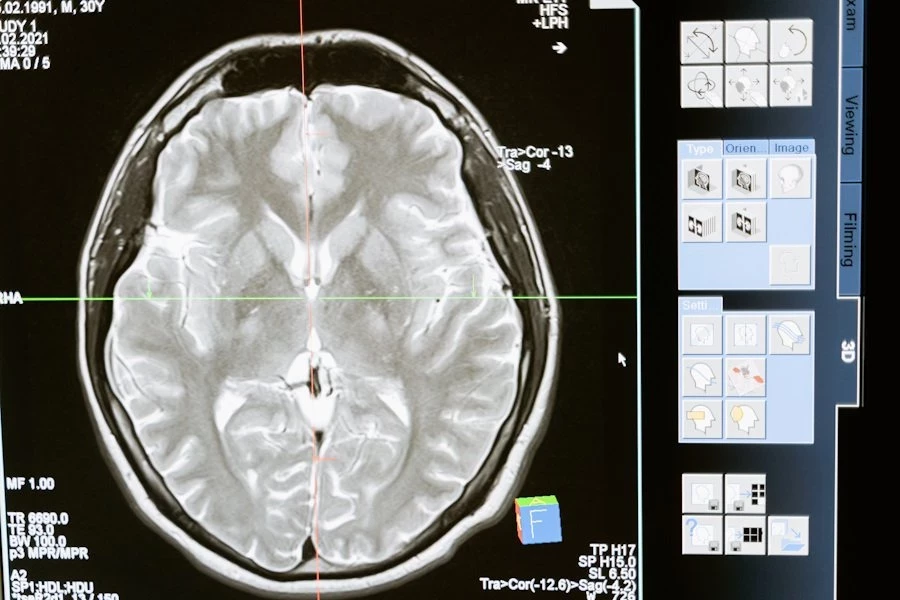

В исследование были включены свыше 170 человек старше 65 лет, не имеющие проблем с когнитивными функциями, которые прошли МРТ головного мозга (измеряли объём гиппокампа), и прошли обследование у стоматологов (оценивался пародонтит). Повторное обследование проводилось через 4 года.